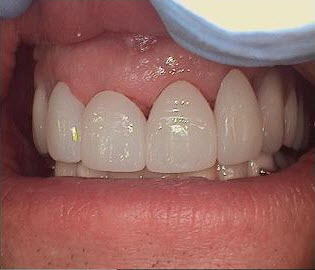

Zirconia Anterior Crowns